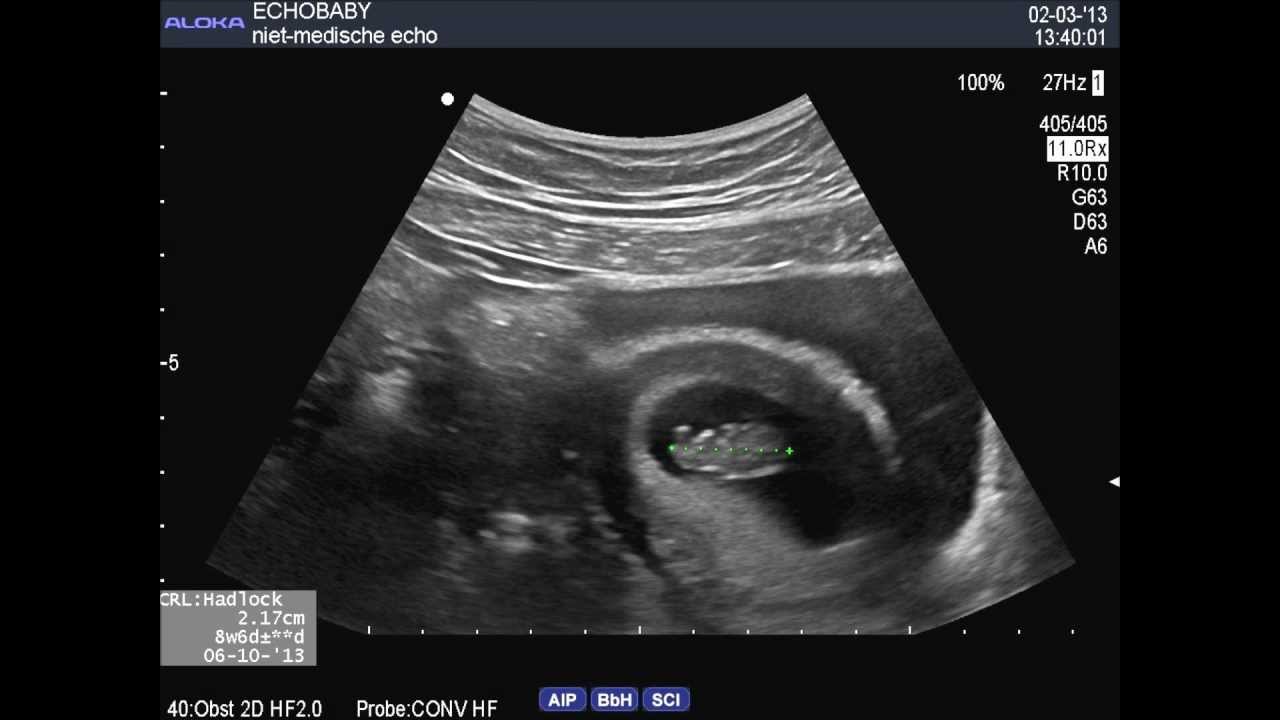

Echografie 1e trimester:rond 11 weken zwangerschapsduur

Tijdens deze echo zult u waarschijnlijk voor de laatste keer uw kindje in zijn geheel op het scherm zien. De voornaamste redenen van deze echo zijn: * bevestigen van de zwangerschap en hartactiviteit * bepalen van de zwangerschapsduur * nagaan of het om één baby of meerdere baby's gaat * opmeten van de nekplooi * opsporen van grote structurele afwijkingen |